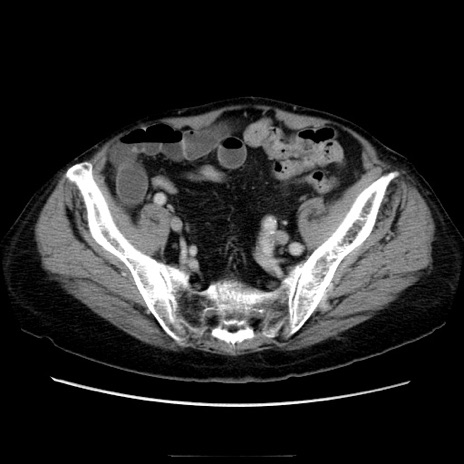

症例21(横断像)

【症例】70歳代男性

【主訴】腹痛

【現病歴】肝硬変・肝細胞癌にてかかりつけの方。約9時間前に食後より腹痛出現。症状が徐々に増悪し、嘔吐出現したため来院。

【既往歴】肝硬変、肝細胞癌(RFA、TACE後)

【身体所見】意識清明、表情苦悶様、BT 36℃、BP 129/78mmHg、P 88bpm、SpO2 97%(RA)、右上腹部から心窩部にかけて圧痛あり、反跳痛なし、筋性防御あり。

【データ】WBC 5800、CRP 0.16